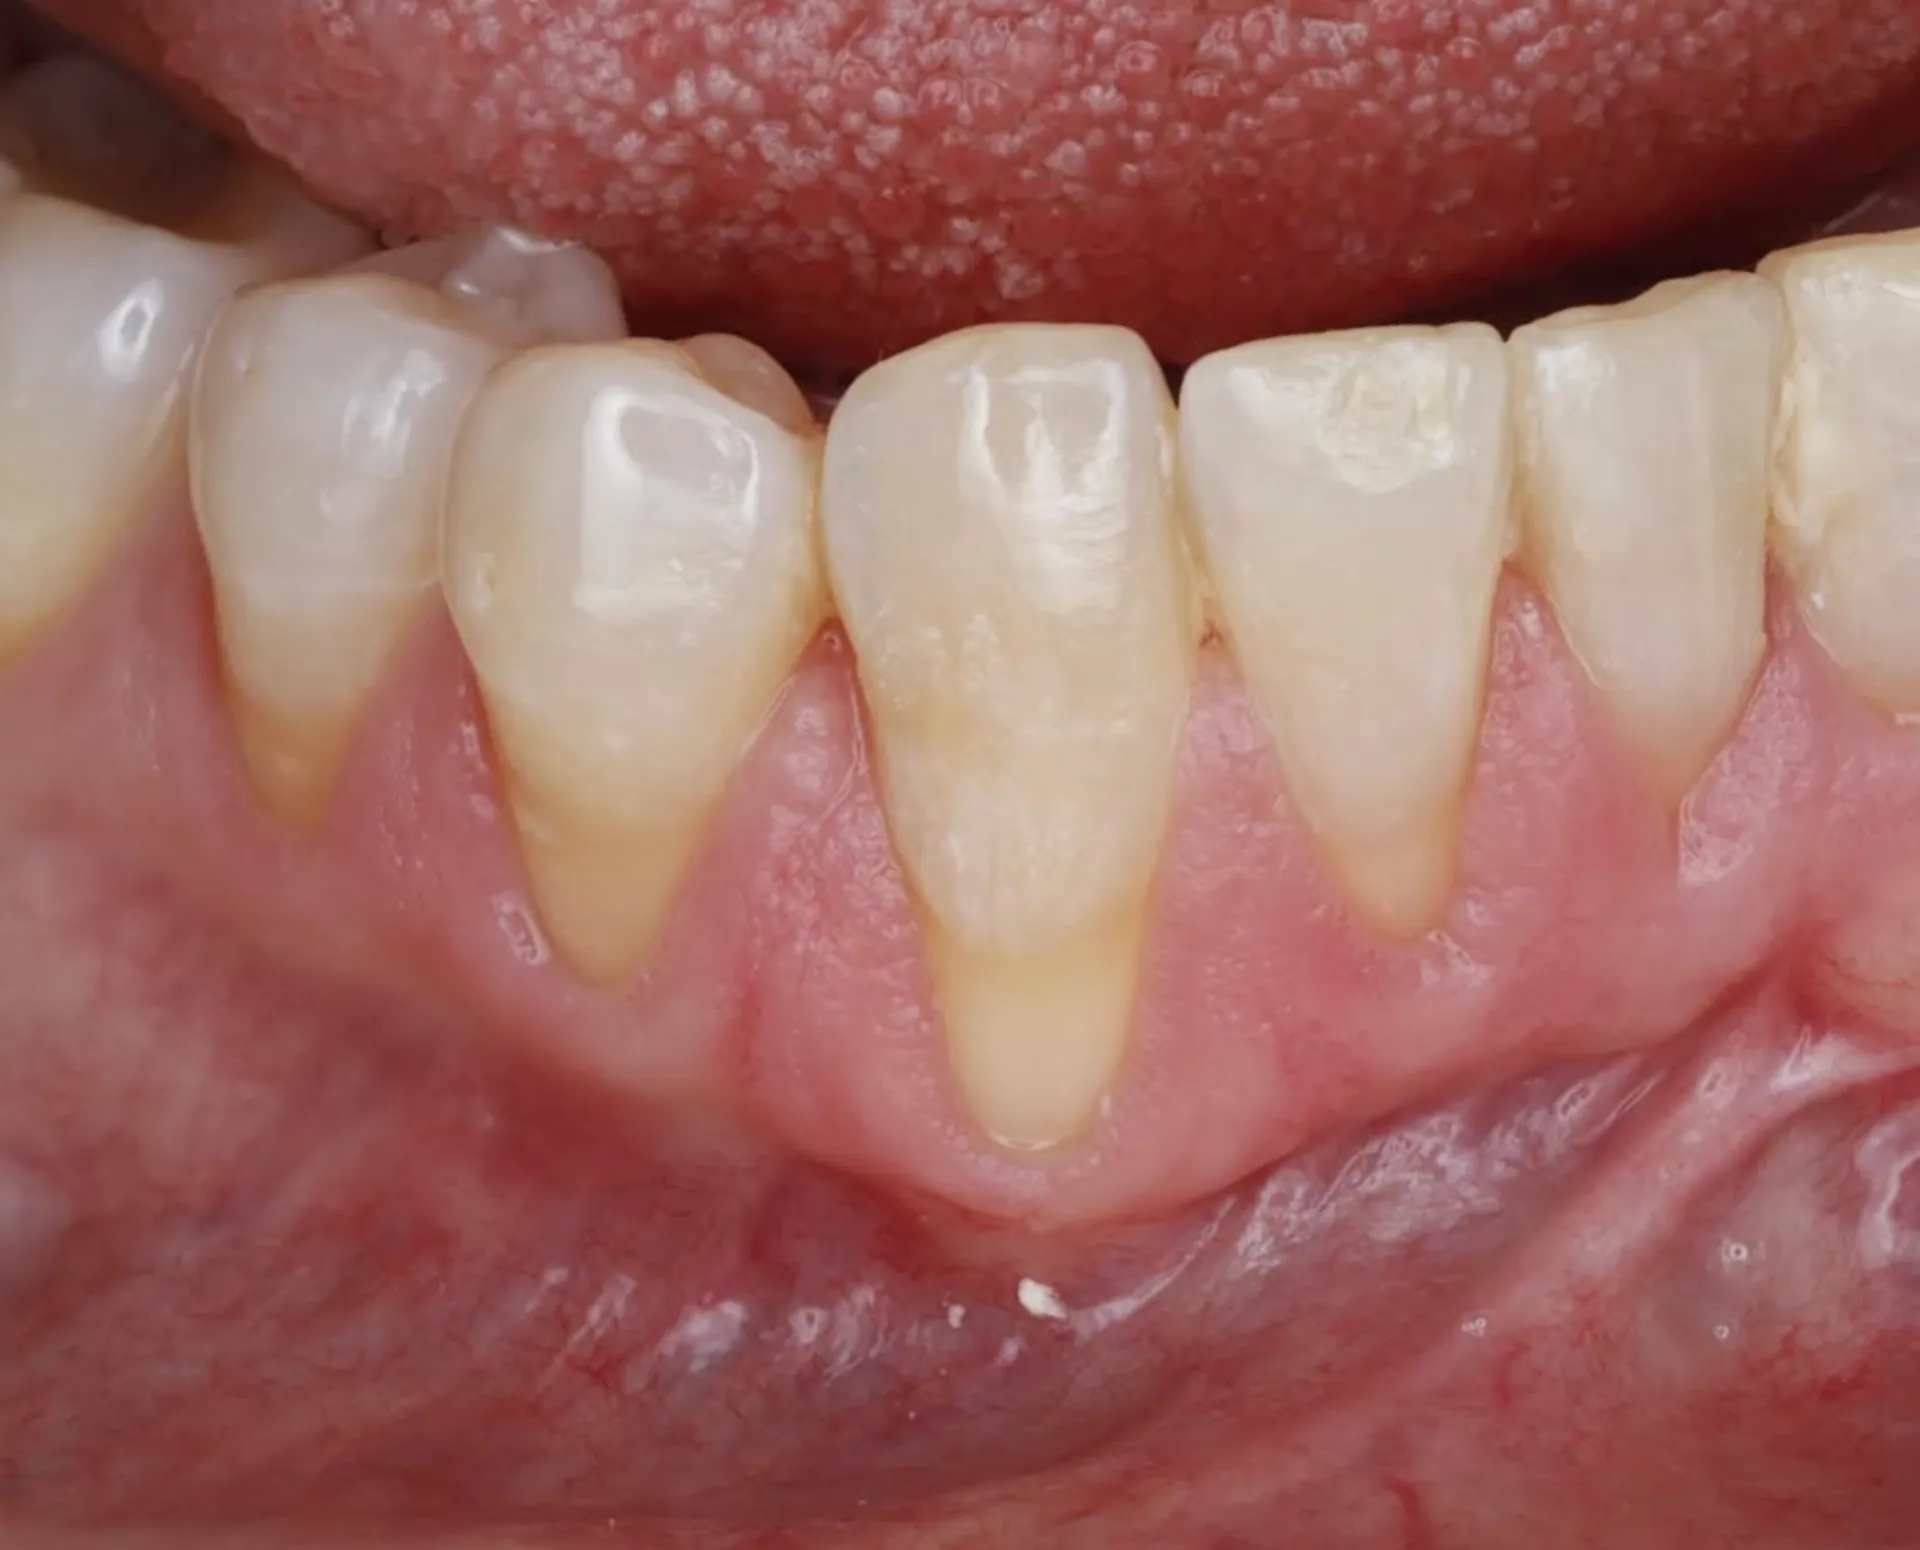

Gum Recession